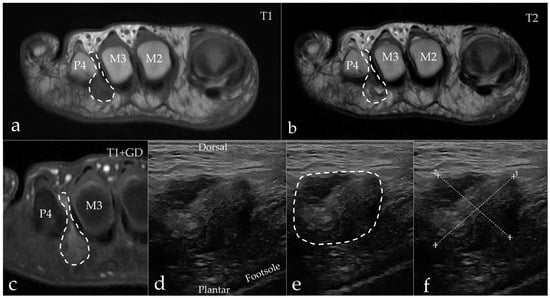

3.2. Imaging Results